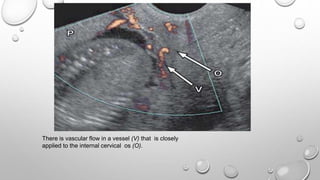

There is vascular flow in a vessel (V) that is closely

applied to the internal cervical os (O).

VASA PREVIA

 Vasa previa refers to the presence of abnormal fetal vessels

within the amniotic membranes that cross the internal cervical

os. These vessels are unsupported by Wharton jelly or

placental tissue and are at risk of rupture when the supporting

membranes rupture; such vessels are also at risk of direct

injury during labor. Rupture of these vessels can lead to

catastrophic fetal hemorrhage.

 The diagnosis of vasa previa is made with Doppler US, which

demonstrates vascular flow within vessels overlying the

internal cervical os .